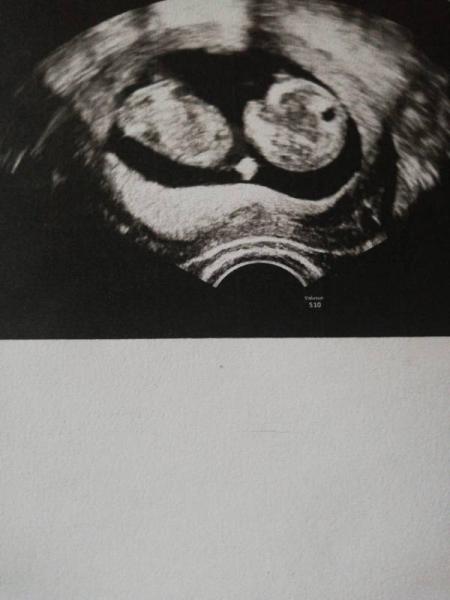

Hallo, ich kenne diese Methode überhaupt garnicht. Wäre jemand so lieb und könnte bei mir mal nachschauen? Es sind 2 Bilder einmal von der 7 Woche und das andere von der 8 Woche.

Ok dann mache ich auch mal mit... Hier mein Bild. Keine Ahnung, ob die gut genug sind. 1. Bild 7. SSW

2. Bild 9.SSW

Ich würde tippen Mädchen da der dottersack aber nicht eindeutig zu sehen ist auch eher ne Vermutung. Wobei wir ja bei allen erst später wissen werden ob die Methode recht gehabt hat. LG nita